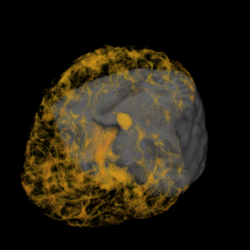

A major task is to implement the abstraction layer for rendering synthetic data, independent of display technology. This may involve use of the MNI's VTk-based IGNS system (IBIS) or build on our own rendering architecture, with low-level rendering engines for each display type, and input taken from existing neuro-visualization tools. In either case, the goal is to integrate the 3D rendering of MRI, fMRI, PET, DTI, and intra-operative ultrasound data, possibly in conjunction with the tracked position of surgical tools, and add modules for additional processing (e.g., feature highlighting, density control, and interactive manipulation/deformation). Rendering strategies must take into account the importance of merging volumetric and surface rendering techniques when dealing with the multiple data sets available.

| cutting plane + MRI | cutting plane + blood vessels | blood vessels + fMRI + PET | blood vessels + fMRI + PET + MRI |